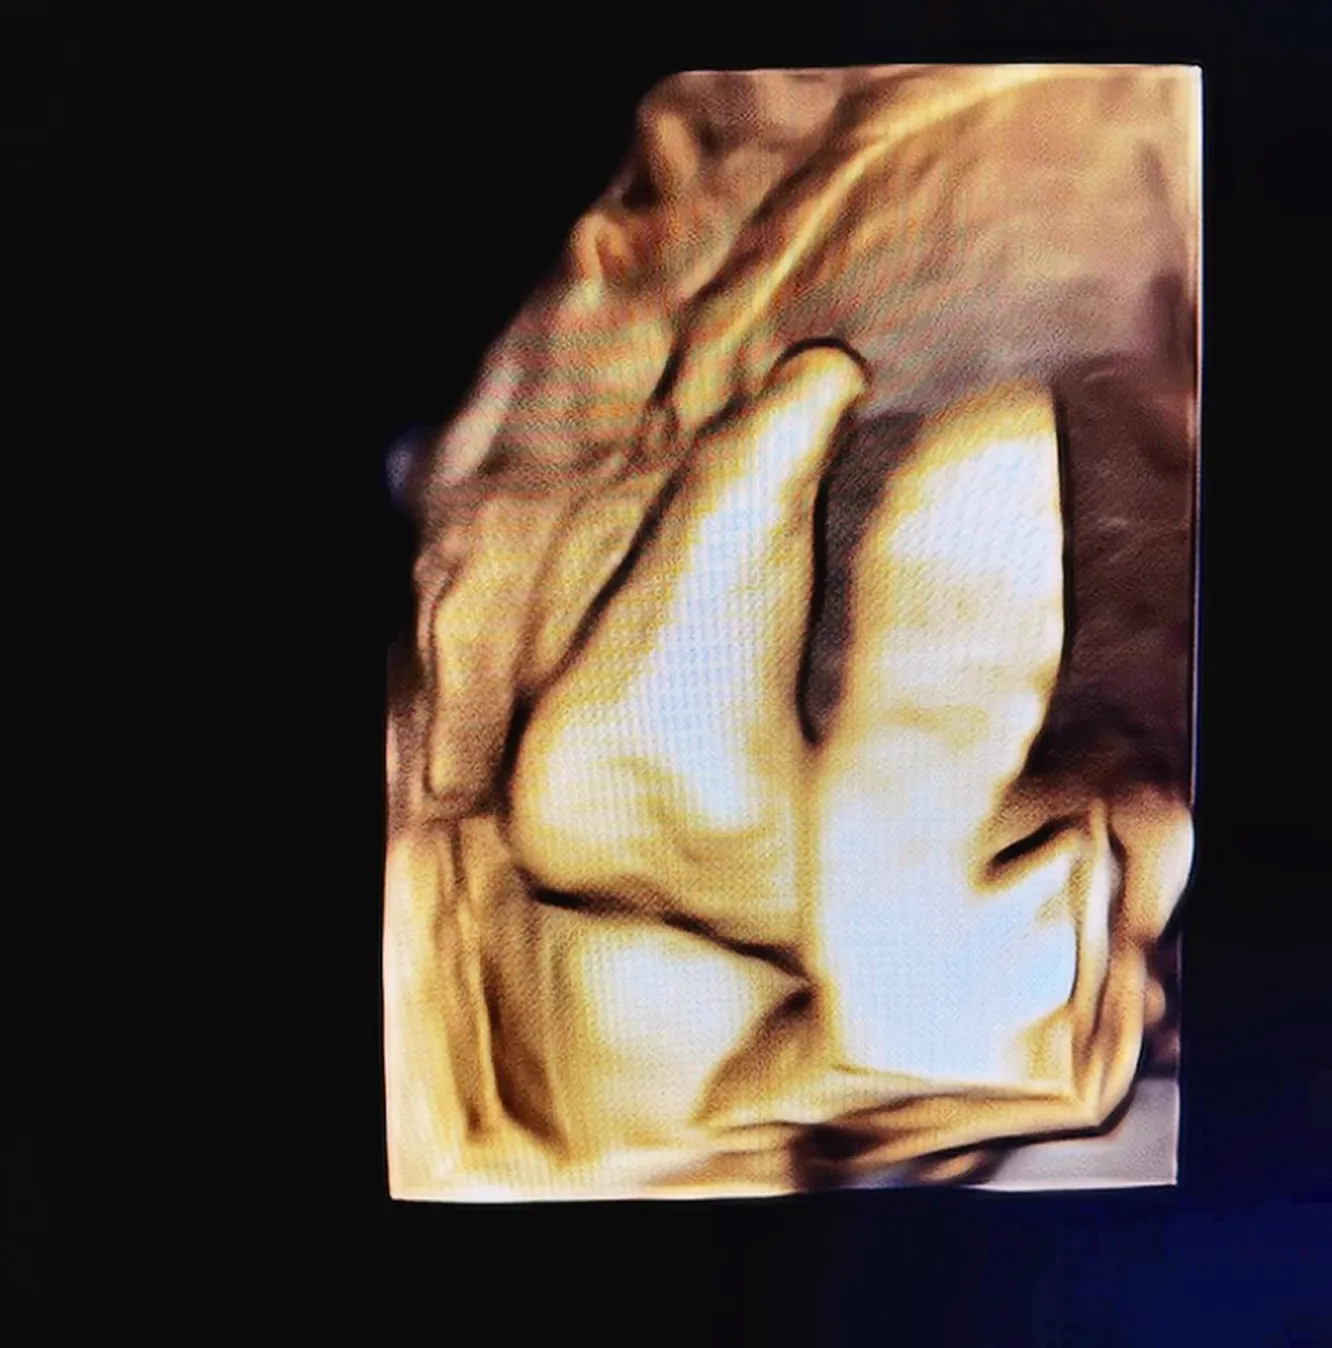

По словам артистки, с самого утра она была в предвкушении. Блогерша надеялась, что малыш покажет личико во время УЗИ. Однако ребенок не захотел и продемонстрировал лишь стопу.

«Повернулся. Ой, ручки и ножки! Мы растем! Уже 1 кг 700 г. Малыш решил продолжить интригу. Показал или показала лишь стопу – 6,5 см», — рассказал Погребняк.